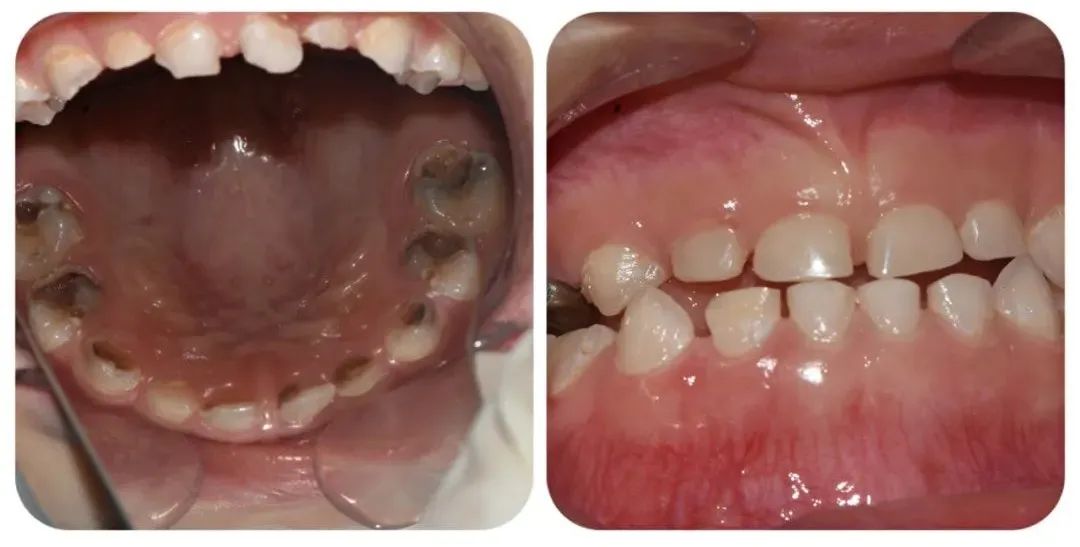

術(shù)中,口腔科主任毛亮與主治醫(yī)師王文涵,在麻醉科醫(yī)護(hù)人員的配合下進(jìn)行手術(shù)。華華在“睡覺”過程中,全程嚴(yán)格監(jiān)控,根據(jù)個(gè)體情況和手術(shù)進(jìn)程,調(diào)整用藥用量,保障手術(shù)安全。歷時(shí)2小時(shí),一次性完成了對(duì)患者多生牙、齲齒、牙髓疾病,殘根及殘冠等患牙的治療。

手術(shù)過程順利,一次性為患兒解決了全部口腔問題,大大減少了患兒就診次數(shù),提高了治療質(zhì)量。術(shù)后第二天,術(shù)后的疼痛和不適已經(jīng)消失了。

(修復(fù)前后對(duì)比)